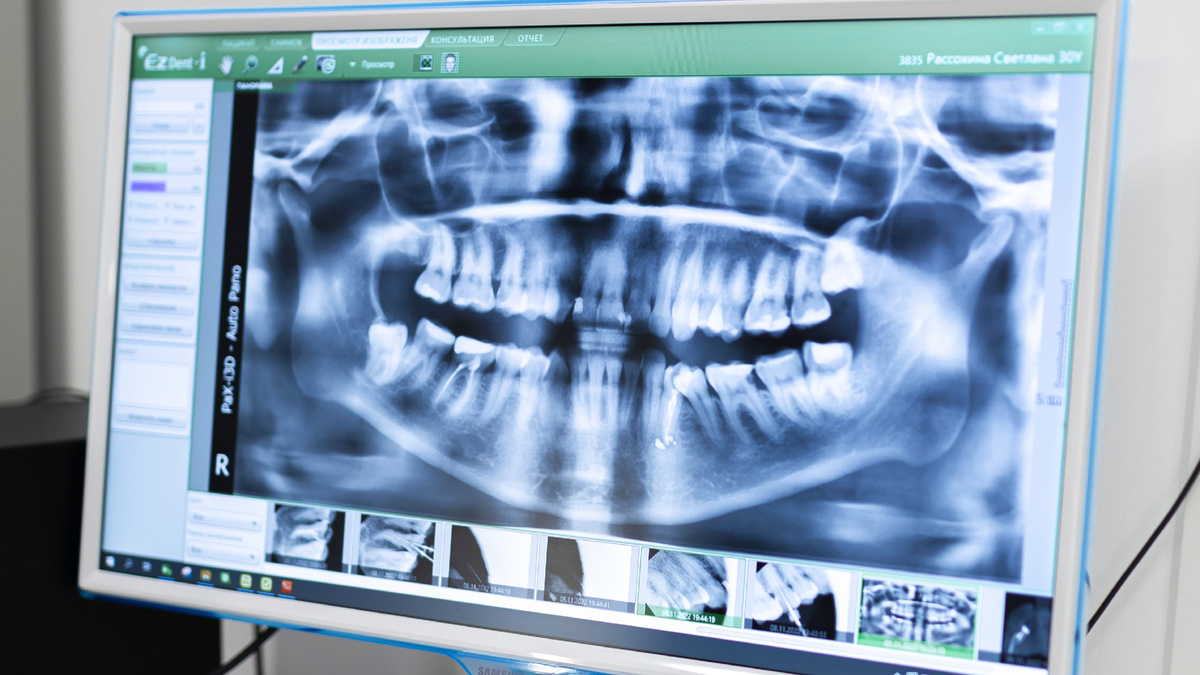

Челюстно-лицевая хирургия — это область медицины тесно связана со стоматологией и способна решить сложные проблемы с прикусом, тяжелыми патологиями зубов и челюсти в целом. В ситуациях, когда помощи стоматологов недостаточно, к лечению подключается челюстно-лицевые хирурги. Что делает челюстно-лицевой хирург? Данное направление хирургии предлагает широкий спектр вариантов лечения пациентов, перенесших травму, значительное смещение зубов, расстройство височно-нижнечелюстного сустава (ВНЧС) и другие серьезные проблемы со здоровьем полости рта, которые могут нуждаться в целенаправленном хирургическом лечении для возвращения им естественной красоты и здоровья зубов. Челюстно-лицевая хирургия решает проблемы, выходящие за рамки привычной стоматологии, а ее методики призваны исправлять врожденные и приобретенные дефекты на уровне костных структур челюсти, лица и шеи. Помимо работы с лицевым скелетом, челюстно-лицевой хирург проводит операции и на мягких тканях лица. Это может быть удаление к

Данное направление хирургии предлагает широкий спектр вариантов лечения пациентов, перенесших травму, значительное смещение зубов, расстройство височно-нижнечелюстного сустава (ВНЧС) и другие серьезные проблемы со здоровьем полости рта, которые могут нуждаться в целенаправленном хирургическом лечении для возвращения им естественной красоты и здоровья зубов.

Челюстно-лицевая хирургия решает проблемы, выходящие за рамки привычной стоматологии, а ее методики призваны исправлять врожденные и приобретенные дефекты на уровне костных структур челюсти, лица и шеи. Помимо работы с лицевым скелетом, челюстно-лицевой хирург проводит операции и на мягких тканях лица. Это может быть удаление кист и новообразований кожи, подкожно-жировой клетчатки и слюнных желез, различные пластики и даже синусотомии.